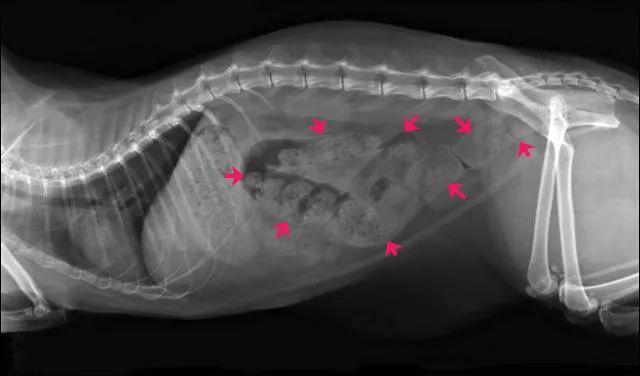

下图片子中,红色箭头部分,都是未排除的屎:

小猫便秘了怎么治疗?